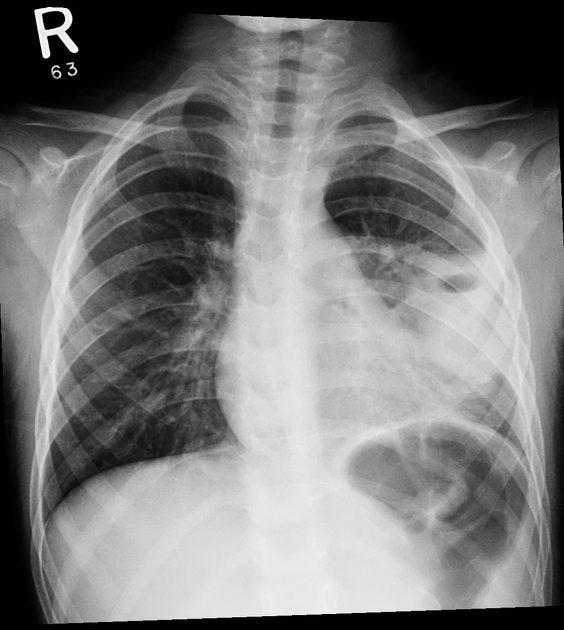

6yo F with cough and fever. Your interpretation?

What is a left lower lobe infiltrates associated with cavitary lesion with an air-fluid level or lung abscess?